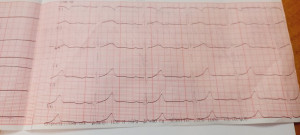

После ЭКГ не дали справку для спорта. Почему?

На ЭКГ написано:

Синусовый ритм

час 85 уд/мин

Суправентрикулярная экстрасистолия

Нормальное направление электрической оси сердца